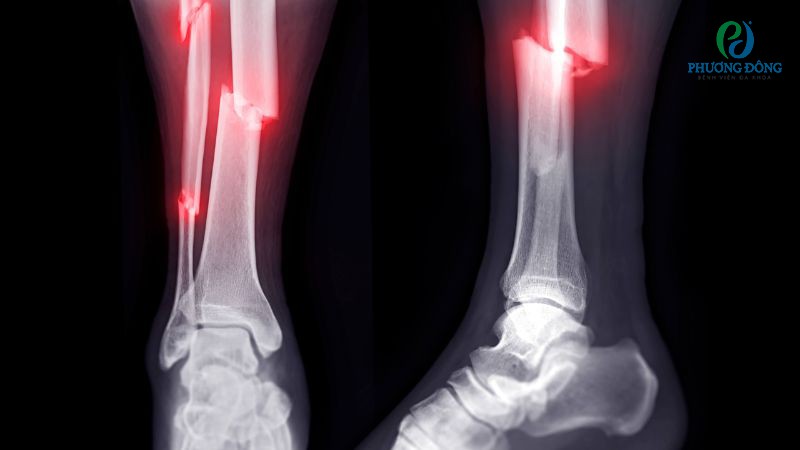

Gãy xương

Gãy xương là dạng chấn thương phổ biến, xảy ra do hệ xương khớp phải chịu một lực tác động mạnh, vượt ngưỡng chịu đựng thông thường. Tùy trường hợp mà xương có có thể tự lành nhờ phương pháp bó bột hoặc can thiệp phẫu thuật chỉnh hình cấu trúc giải phẫu.

Gãy xương là một dạng chấn thương phổ biến, thường do chịu lực tác động mạnh

- Chụp X-quang với trường hợp nghi ngờ gãy xương, khớp bị viêm, thoái hóa hoặc vấn đề bất thường ở cấu trúc xương.